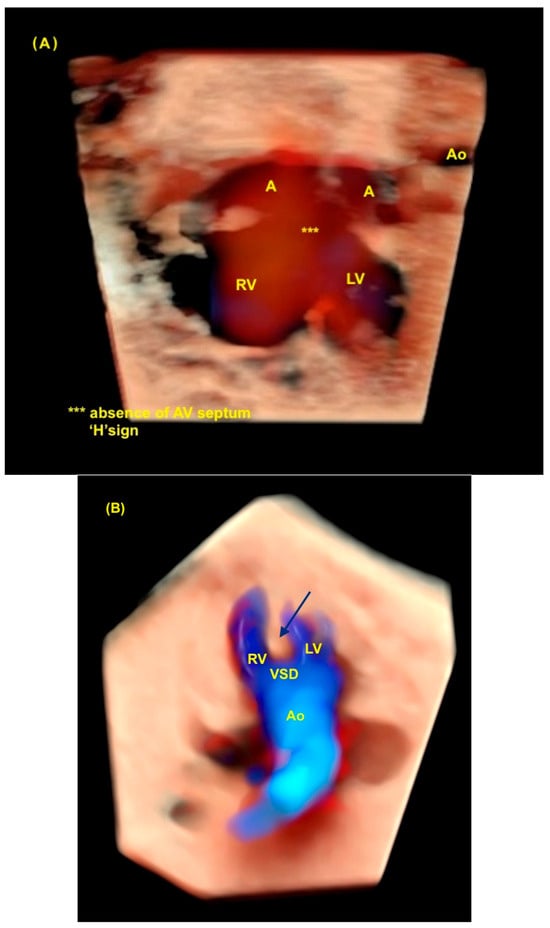

Figure 8.

Spatiotemporal Image Correlation with HDlive Silhouette and HDlive Flow techniques of fetus with atrioventricular septal defect and tetralogy of Fallot. (A) Note the “H” sign (***) during diastole in the four-chamber view of the heart. The “H” sign is an important clue to the ultrasound diagnosis of total atrioventricular septal defect. (B) Note the superposition of the aorta in the ventricular outflow tract view due to the dextroposition of the aorta, which is an important clue to suspect the diagnosis of tetralogy of Fallot (interventricular septum—blue arrow). LV: left ventricle; A: atrium (left and right); RV: right ventricle; AV: atrioventricular; Ao: aorta; VSD: ventricular septal defect.